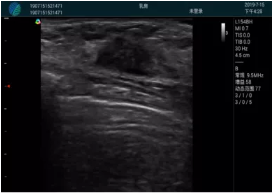

清晰顯示腺體內(nèi)低回聲快影,邊界清晰,包膜較光滑

確定進(jìn)針路徑并實(shí)時(shí)監(jiān)測抽吸針與腫塊位置關(guān)系

抽吸針進(jìn)入腫塊內(nèi)部進(jìn)行旋切

抽吸過程中可見腫塊明顯縮小,并根據(jù)腫塊位置改變針道位置

抽吸旋切后再進(jìn)行超聲復(fù)查,原腫塊區(qū)域未見殘留組織及出血